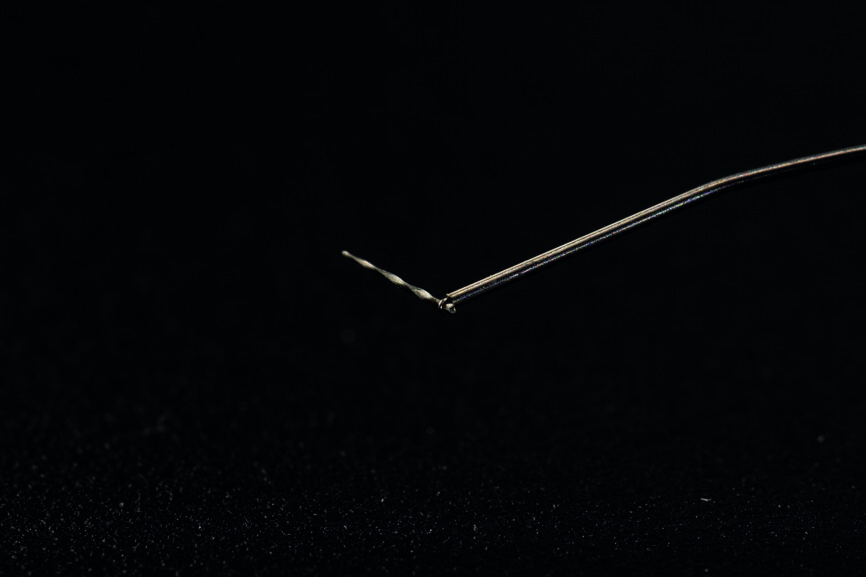

Le système de lasso choisi est le dispositif EndoCowboy en raison des caractéristiques et de la résistance du fil (fil de 0,1 mm en acier inoxydable étiré ayant une excellente résistance à la rupture, et tube de 0,4 mm ; Köhrer Medical Engineering). Conformément aux instructions du fabricant (Figs. 8 et 9), le dispositif est manipulé par deux praticiens travaillant en commun — l’un étant chargé d’observer au microscope la position de la boucle du lasso autour du fragment fracturé, et l’autre de manipuler le dispositif (serrage du lasso autour du fragment. Après avoir solidarisé le fragment et la boucle, l’ensemble est alors retiré par de légers mouvements de va-et-vient verticaux (Figs. 10–13). Tous les canaux sont instrumentés avec des limes D-Finder de taille 8, 10, 12 et 15 (MANI) pour obtenir manuellement une trajectoire de glissement (glide path). Le nettoyage et la mise en forme de tous les canaux radiculaires sont réalisés à l’aide de limes Silk (MANI) de taille croissante (jusqu’à 25/0.06) et du moteur endodontique Tri Auto ZX2 (Morita). Un protocole d’irrigation à l’hypochlorite de sodium à 5,25 % est assuré tout au long du traitement. L’irrigation finale est accomplie avec une solution d’EDTA à 17 % et d’hypochlorite de sodium à 5,25 %, activée par une technique manuelle d’activation dynamique. La technique de condensation hydraulique est utilisée pour réaliser l’obturation avec des cônes de gutta-percha à 4 % et le ciment de scellement BioRoot RCS (Septodont) (Figs. 14–16). La cavité pulpaire est scellée au moyen d’un ciment verre ionomère modifié par adjonction de résine, Ionoseal (VOCO), et une restauration provisoire est préparée.

Fig. 8 : Mise en place du dispositif de lasso EndoCowboy autour du segment coronaire du fragment.

Fig. 9 : Fragment retiré encore attaché à la boucle du fil métallique